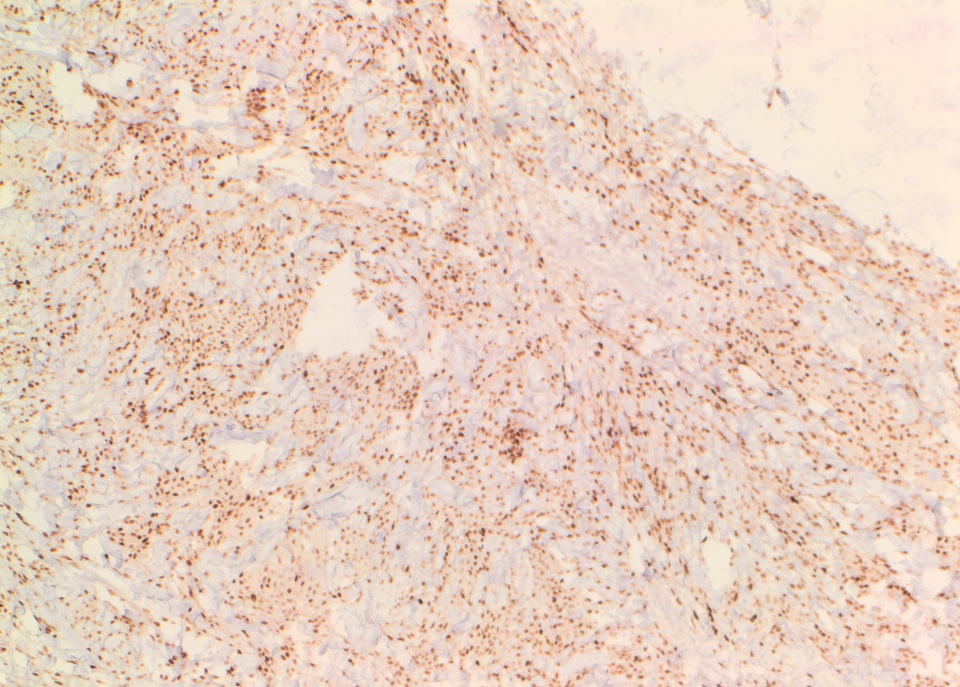

The tumor cells were strongly positive for CD34, ER and PR.

The conventional histologic appearance is of bland fibroblast-like spindle cells with relatively short, stubby nuclei. The cells are interspersed between collagen bundles and a variable amount of adipose tissue. The stroma can show hyalinization and / or myxoid change. Mast cells may be conspicuous (Goldblum: Enzinger and Weiss's Soft Tissue Tumors, 6th ed, 2013, Am J Surg Pathol 2016;40:361). Several different variants of MTMF have been described: cellular, infiltrating, collagenized / fibrous, lipomatous, myxoid, epithelioid and deciduoid-like. Areas of smooth muscle, bone and cartilage can be seen (Am J Surg Pathol 2009;33:1085). Rare tumors may show a neurilemmoma-like pattern. "Symplastic" or degenerative cytologic atypia - enlarged, hyperchromatic, multinucleated cells - can be present (Am J Surg Pathol 2016;40:361).

The tumor cells were strongly positive for CD34, ER and PR.

The conventional histologic appearance is of bland fibroblast-like spindle cells with relatively short, stubby nuclei. The cells are interspersed between collagen bundles and a variable amount of adipose tissue. The stroma can show hyalinization and / or myxoid change. Mast cells may be conspicuous (Goldblum: Enzinger and Weiss's Soft Tissue Tumors, 6th ed, 2013, Am J Surg Pathol 2016;40:361). Several different variants of MTMF have been described: cellular, infiltrating, collagenized / fibrous, lipomatous, myxoid, epithelioid and deciduoid-like. Areas of smooth muscle, bone and cartilage can be seen (Am J Surg Pathol 2009;33:1085). Rare tumors may show a neurilemmoma-like pattern. "Symplastic" or degenerative cytologic atypia - enlarged, hyperchromatic, multinucleated cells - can be present (Am J Surg Pathol 2016;40:361).